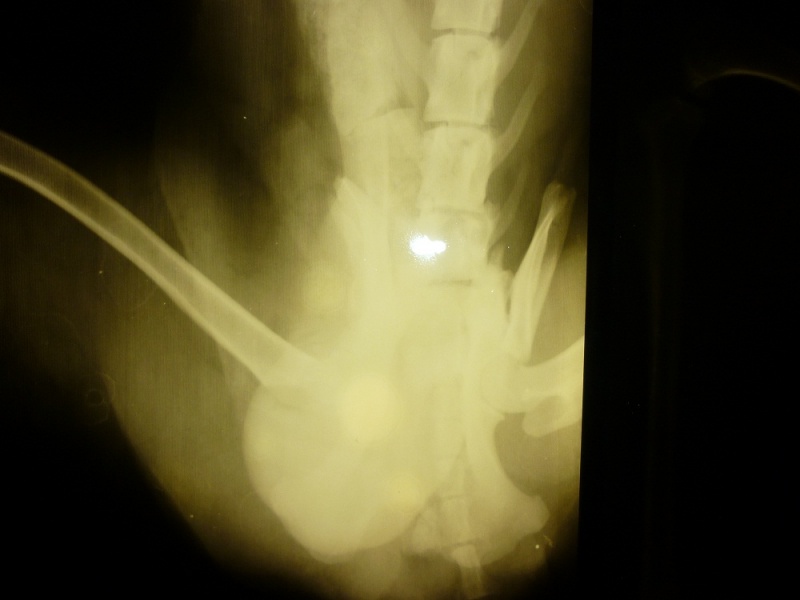

Друзья,свозили мы с Леной Филю в Бэст.У пацанёнка перелом таза,лапы целые,что-то там с яичками ещё,но всё излечимо.Смена сегодня ужасная(да простят меня модераторы),но Слава Богу случай не смертельный!Предложили операцию,хотя и без этого,сказали, всё срастётся,но пёс будет хромать.Кураторы решили операцию не делать.Лечение псинке прописали.Мы увезли его обратно в цех.Там тепло,женщины,которые за ним ухаживают, такие заботливые

Пока что мои расходы на ветклинику и лечение составили 2,5 тысячи. Это не считая подкладных пеленок и супов на очень густом наваристом бульоне. А у меня еще своих три собаки. Сегодня уже было собрались везти на операцию. Денег хоть и маловато насобирали (знакомые), да медлить с этим думали как то опасно. Отвезти попросила знакомую девочку. А она когда-то училась в сельхозакадемии. Сейчас собаками занимается. В общем посмотрела она снимки, сказала что ничего на них не видит. А я тоже как-то на них ничего не нахожу. Хоть и не спец, а в интернете снимки с переломами на эту тему просмотрела. Там действительно очень наглядно показано. Привезла эта моя знакомая своих знакомых, положили они его на другой бок и очень долго и осторожно прощупывали. Герой наш лежал довольно спокойно. Однозначно кокушки себе отморозил напрочь. Поэтому кастрировать его однозначно придется. А в остальном... операцию решили не делать. Если и есть повреждения, то они со временем заживут.У меня почему-то у самой было предчувствие, что отвезем, разрежут его, почем зря. Ну вот вроде и все. Если кто желает помочь, буду очень признательна, потому что уход еще предстоит очень долгий. Всем предложившим помощь отпишусь.

Возили сегодня Филю в ЦВК. Сделали новые снимки. Прогноз неутешительный. В результате травмы задет спинной мозг. Чувствительность задних конечностей практически равна нулю.Очень хочется верить что все таки он сможет хотя бы на трех лапах ходить. Сегодня по приезду домой он умудрился выпрыгнуть с заднего сиденья машины и очень быстро карабкаться через дорогу. До слез пробрало!!! Буду бороться дальше за его здоровье. По прежнему для этого нужны средства.